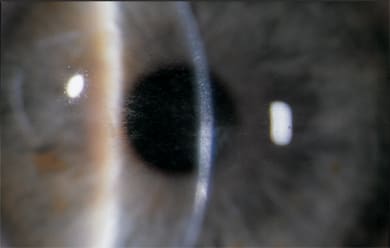

COURTESY OF WILLIAM TRATTLER, MD.

Incomplete LASIK flap, with scarring within the visual axis.